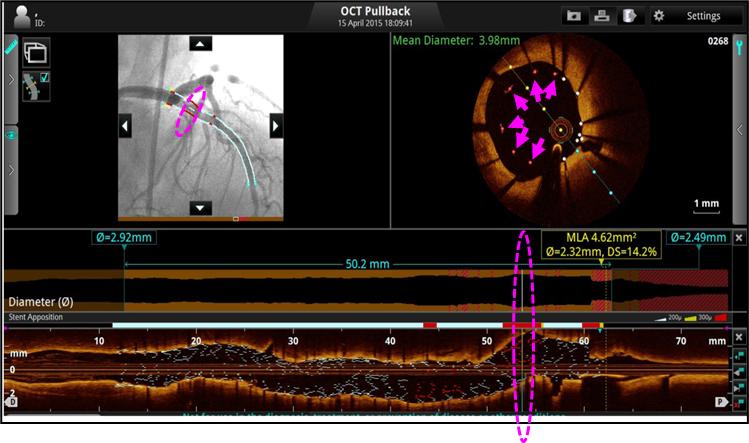

1、Angio-OCT同步定位病变,精准指导支架置入。

A、快速精准定位:Angio-OCT同步锁定病变,精准指导支架植入。

只需2~3秒时间就能够实现造影图像与OCT图像的同步融合显示;

两种图像同步锁定病变位置,直观显示病变形态和相关解剖学信息,让支架定位和评估更加准确。